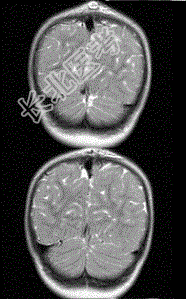

- 单项选择题男孩,1岁。有头皮损伤史, CT检查,最可能的诊断是

A、脑膨出

B、胼胝体发育不全

C、Dandy-Walker综合征

D、狭颅症

E、脑积水